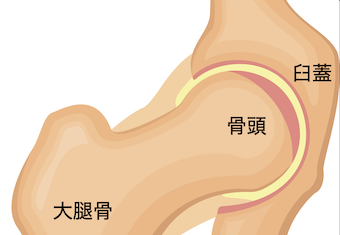

脱臼しやすい股関節で生まれてきた児が、間違った方法で育てられることによって、徐々に脱臼が進行します。出生時に脱臼していることは少ないので、最近は「先天性股関節脱臼」ではなく「発育性股関節形成不全」と呼ばれています。

脱臼しない育て方

出生直後の股関節は、臼蓋が浅くて不安定な状態です。その後、骨頭が臼蓋の中で自由に動くことで、臼蓋が深くなり脱臼しない股関節に成長します。上手に臼蓋を育てるためには、股・膝関節を軽く曲げた状態で自由に動かせるようにすること、そして無理に関節を伸ばしたり、固定して動きを制限しないことが大切です。特に出生直後〜2ヶ月までが重要だといわれています。